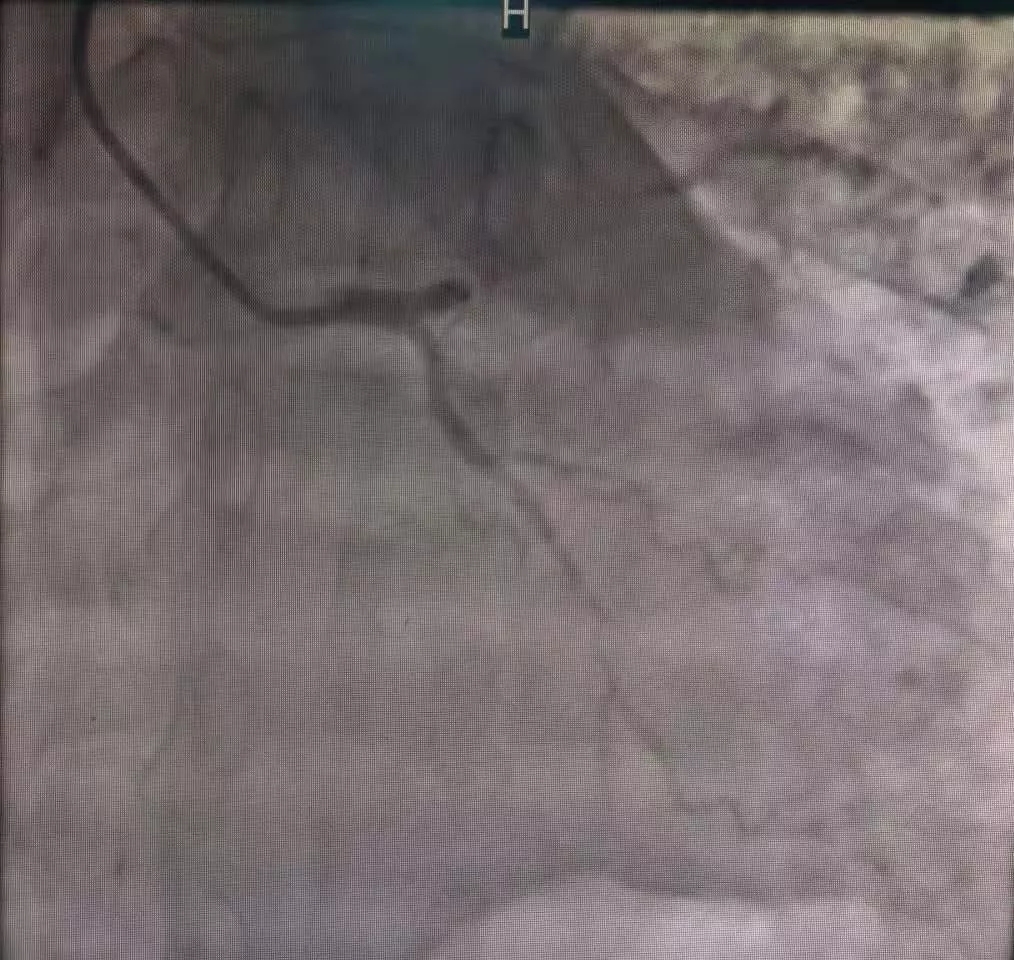

99次除颤抢救 4天3夜轮流守候 创造心内奇迹